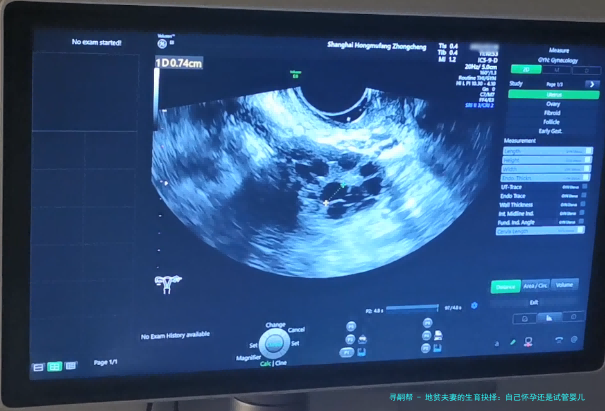

地贫夫妻的生育抉择:自己怀孕还是试管婴儿?

接下来,咱们聊聊试管婴儿技术。试管婴儿,学名叫体外受精-胚胎移植,特别是其中的PGD(植入前遗传学诊断)技术,简直就是地贫夫妻的救星。简单来说,医生可以在实验室里对胚胎进行基因筛查,只选择没有地贫基因的健康胚胎移植到子宫里。这样,就能大大降低孩子患病的风险。在我看来,这就像是为生育之路装上了“导航系统”,让你避开那些遗传陷阱。举个例子,前面提到的小张和小李后来选择了试管婴儿,通过PGD筛查,他们成功生下了健康的宝宝,现在家庭生活美满。不过,试管婴儿也有它的缺点,比如费用较高,过程可能比较繁琐,而且成功率不是100%。但总的来说,对于高风险的地贫夫妻,它提供了一个更安全的选项。